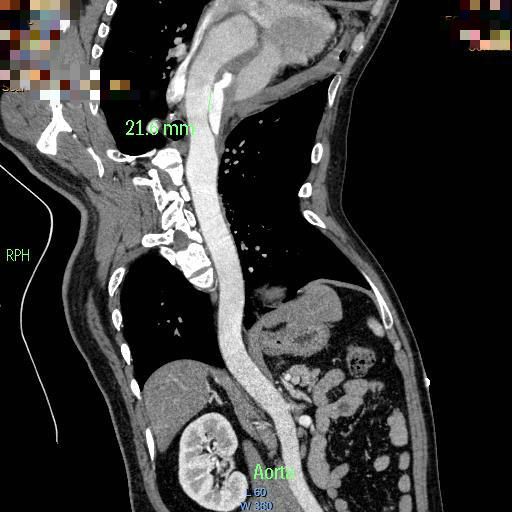

出现此种症状时需要完成的检查包括常规的心电图、心肌酶、凝血功能,上述检查主要用于鉴别诊断,主要与心肌梗塞、肺动脉栓塞相鉴别。明确诊断需要行胸腹主动脉的CTA检查(CT血管成像)。确诊之后需要及时转入血管外科,首先要做的就是镇痛、控制血压和心率,然后依据CTA结果确定患者病变分型,依据分型制定手术方案。

目前有两种分型方式(如上图所示),临床中更常用的是Stanford分型,B型基本可通过覆膜支架的植入完成微创治疗,而A型往往提示病变更复杂,有些患者需要行传统开刀手术,但随着腔内器械及手术技术的提高和创新,目前大多A型病变的患者可通过烟囱、开窗或者分支支架的方式完成腔内治疗,极大降低了手术创伤和风险,提高了患者生存率。